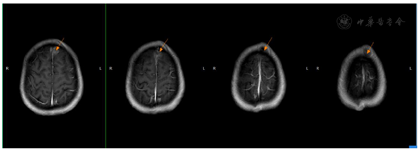

2018年7月2日患者第二次我院住院诊治,此时患者仍有发热,伴额头、左颈部,胸壁多处等多部位脓肿形成,胸部CT、颈部CT、头颅MR、腹部MR较前均有进展,多部位脓肿形成(图1,图2,图3,图4),入院后予B超引导下胸壁脓肿穿刺引流(图5),穿出脓液60 ml左右,穿刺液涂片抗酸阳性,穿刺液培养提示:非结核分枝杆菌生长,菌种鉴定提示疑似胞内分枝杆菌,患者既往血培养鉴定提升哥伦比亚分枝杆菌,考虑患者为播散性哥伦比亚分枝杆菌病,根据MIC结果予调整方案为AmRClrMfxE抗分枝杆菌治疗,后因耳鸣停Am,因药物热不能排除停用R,后调整方案为ClrMfxELzd+替加环素抗分枝杆菌感染,地塞米松减轻炎性反应,治疗后患者体温恢复正常,予出院回当地继续ClrMfxELzd+多西环素抗分枝杆菌治疗。

哥伦比亚分枝杆菌感染临床表现一般无特异性,一般以感染最常见感染部位为肺部,此外还发生于淋巴结、骨、皮肤、胃肠道等部位[2]。哥伦比亚分枝杆菌病肺部受累的影像学表现报道也较少,多无特异性,胸部CT可表现多种征象,如结节、实变、支气管扩张、磨玻璃密度影、纤维索条影、多发空洞、纵隔淋巴结肿大等[3,4]。哥伦比亚分枝杆菌病淋巴结病变表现为淋巴结肿大,CT增强扫描可表现为环状强化[5],骨关节受累可表现为多发溶骨性骨质破坏[6],本例表现播散性感染,肺部表现为双肺粟粒样改变,伴结节条索影,治疗后期出现两侧胸腔积液,纵隔多发淋巴结增大,环形强化不明显。本病例以骨骼侵犯起病,颅骨、颈椎、胸椎、腰椎、肋骨、髋关节,股骨均发生破坏,以侵蚀性溶骨改变为主,伴骨破坏处脓肿形成。

1.播散性哥伦比亚非结核分枝杆菌病(双肺、胸膜、骨、皮下软组织、脑、脑膜) ;